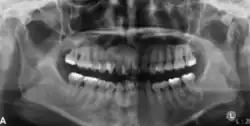

Radiographically, COF appears as a well-defined unilocular lesion. In large mandibular cases, it may cause downward bowing of the inferior border.[13] Tooth displacement is common, while root resorption is less frequently observed.[13] If untreated, the lesion can grow substantially. Surgically, COF is usually well-demarcated from the surrounding bone and often easily enucleated. Some lesions may also exhibit a distinct capsule.[11]

In its early stages, central ossifying fibroma (COF) appears as a small, well-defined radiolucent lesion due to its fibrous tissue content. Differential diagnoses at this stage include periapical pathology, central giant cell granuloma, and ameloblastoma.[22][23] As the lesion matures, it exhibits a mixed radiolucent-radiopaque appearance due to progressive calcification.[22] At this stage, it should be differentiated from other mixed jaw lesions such as fibrous dysplasia, calcifying epithelial odontogenic tumour, adenomatoid odontogenic tumour, and condensing osteitis.[22] In its mature form, COF may appear predominantly radiopaque, resembling lesions like odontomas, osteoblastomas, or osteosarcomas radiographically.

COF typically presents with well-defined, smooth, and often corticated borders. As a central lesion, it originates within the medullary bone and expands concentrically in all directions.[24] With growth, it may cause tooth displacement, root resorption, inferior displacement of the mandibular canal, and loss or alteration of the lamina dura of adjacent teeth.[25]

In conclusion, COF most commonly occurs in the mandible and expands from a central epicenter. Radiographically, it presents as a well-defined mixed-density lesion,[26] and Cone Beam CT (CBCT) plays a crucial role in its accurate diagnosis and assessment.